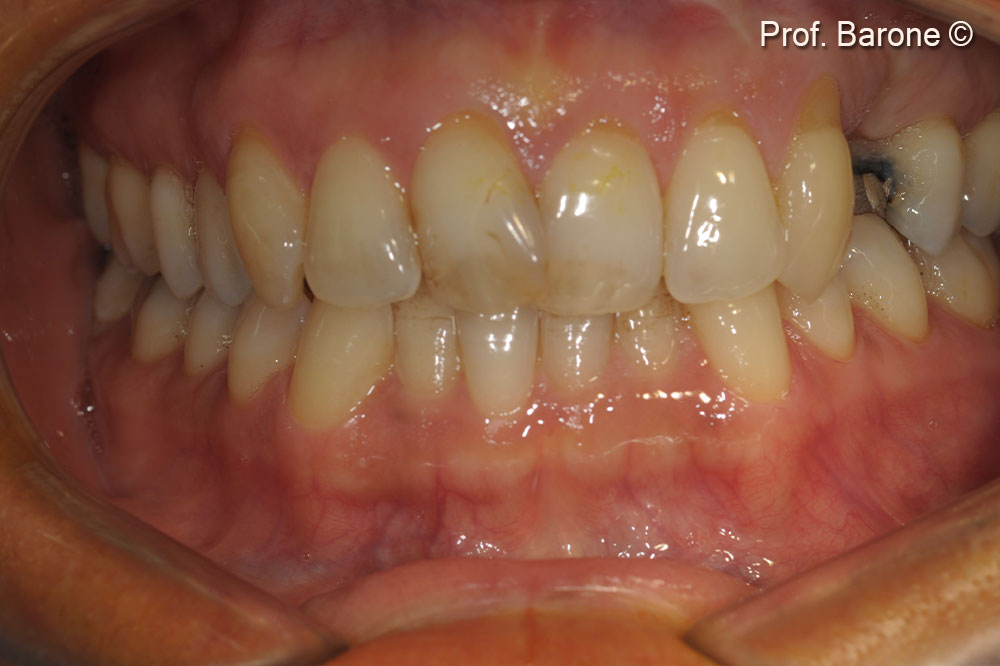

Clinical pre-operative frontal view